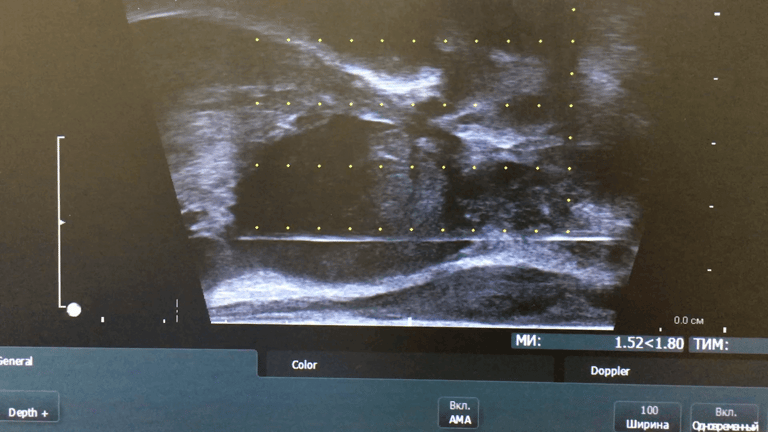

Для діагностики раку передміхурової залози проводиться трансректальна або промежина (трансперинеальна) біопсія, що, за Європейськими стандартами, має обов’язково робитися під УЗД контролем.

Відповідно до рекомендацій Європейської асоціації урології біопсія передміхурової залози під контролем УЗД є стандартною діагностичною процедурою. Лікарю необхідно лише обрати один із двох способів виконання цієї маніпуляції - трансректальний чи промежинний.

Відео: промежинна біопсія простати під УЗД контролем

Про важливу роль аналізу крові на ПСА та мультипараметричної МРТ, як проходить процедура та чому промежинна біопсія простати краща за трансректальну розповідає у відео д.мед.н., лікар-онкоуролог Юрій Васильович Вітрук.

Процедура промежинної біопсії загалом триває до 10 хвилин в залежності від кількості виконаних точок взяття біопсії.

В нашому «Центрі сучасної урології», як правило, біопсія проводиться під внутрішньовенним загальним знеболенням – і проводиться саме промежинна біопсія передміхурової залози за стандартом з 12 ділянок (6 з лівої і 6 з правої долі передміхурової залози).